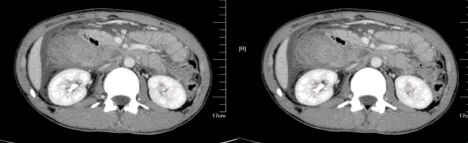

大肠癌

大肠癌是常见的恶性肿瘤,包括结肠癌和直肠癌。大肠癌的发病率从高到低依次为直肠、乙状结肠、盲肠、升结肠、降结肠及横结肠,近年有向近端(右半结肠)发展的趋势。其发病与生活方式、遗传、大肠腺瘤等关系密切。发病年龄趋老年化,男女之比为1.65:1。

升结肠癌并广泛转移